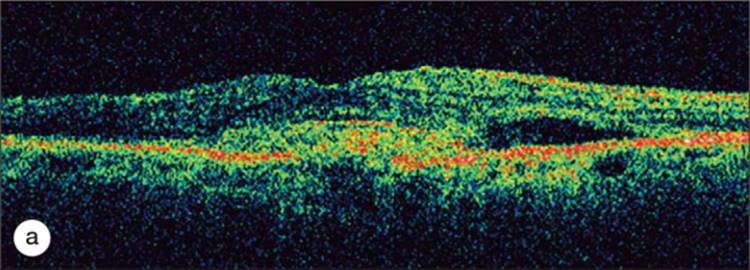

OCT is helpful in confirming the diagnosis as well as quantifying the amount of macular distortion present. It is often quite useful in following the patients in the pre- and postoperative stages. Figure 130.9 demonstrates a case of epiretinal membrane causing decreased vision with images of the same patient after epiretinal membrane peeling.

Click to view full size figure

FIGURE 130.9 (a) demonstrates an epiretinal membrane causing distortion of macular anatomy with loss of the foveal depression and thickening of the retina. The epiretinal membrane is easily identified as the highly reflective structure lying on the surface of the retina. (b) Four months after membrane peeling, the patient's macular anatomy has returned to near normal with return of a foveal depression. One can appreciate the extent of the epiretinal membrane peeling by noticing the residual membrane on the right side of the image.